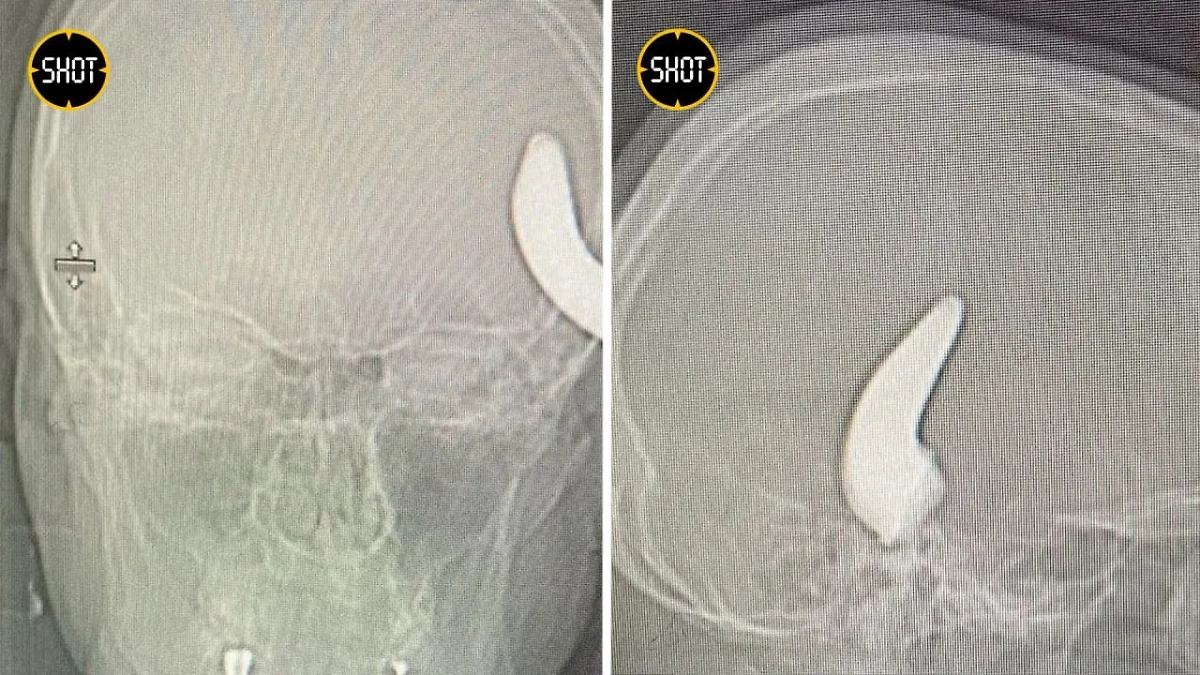

Металлический крюк, который едва не убил петербуржца. Обложка © Telegram / SHOT

Металлический крюк в черепе петербуржца. Фото © Telegram / SHOT